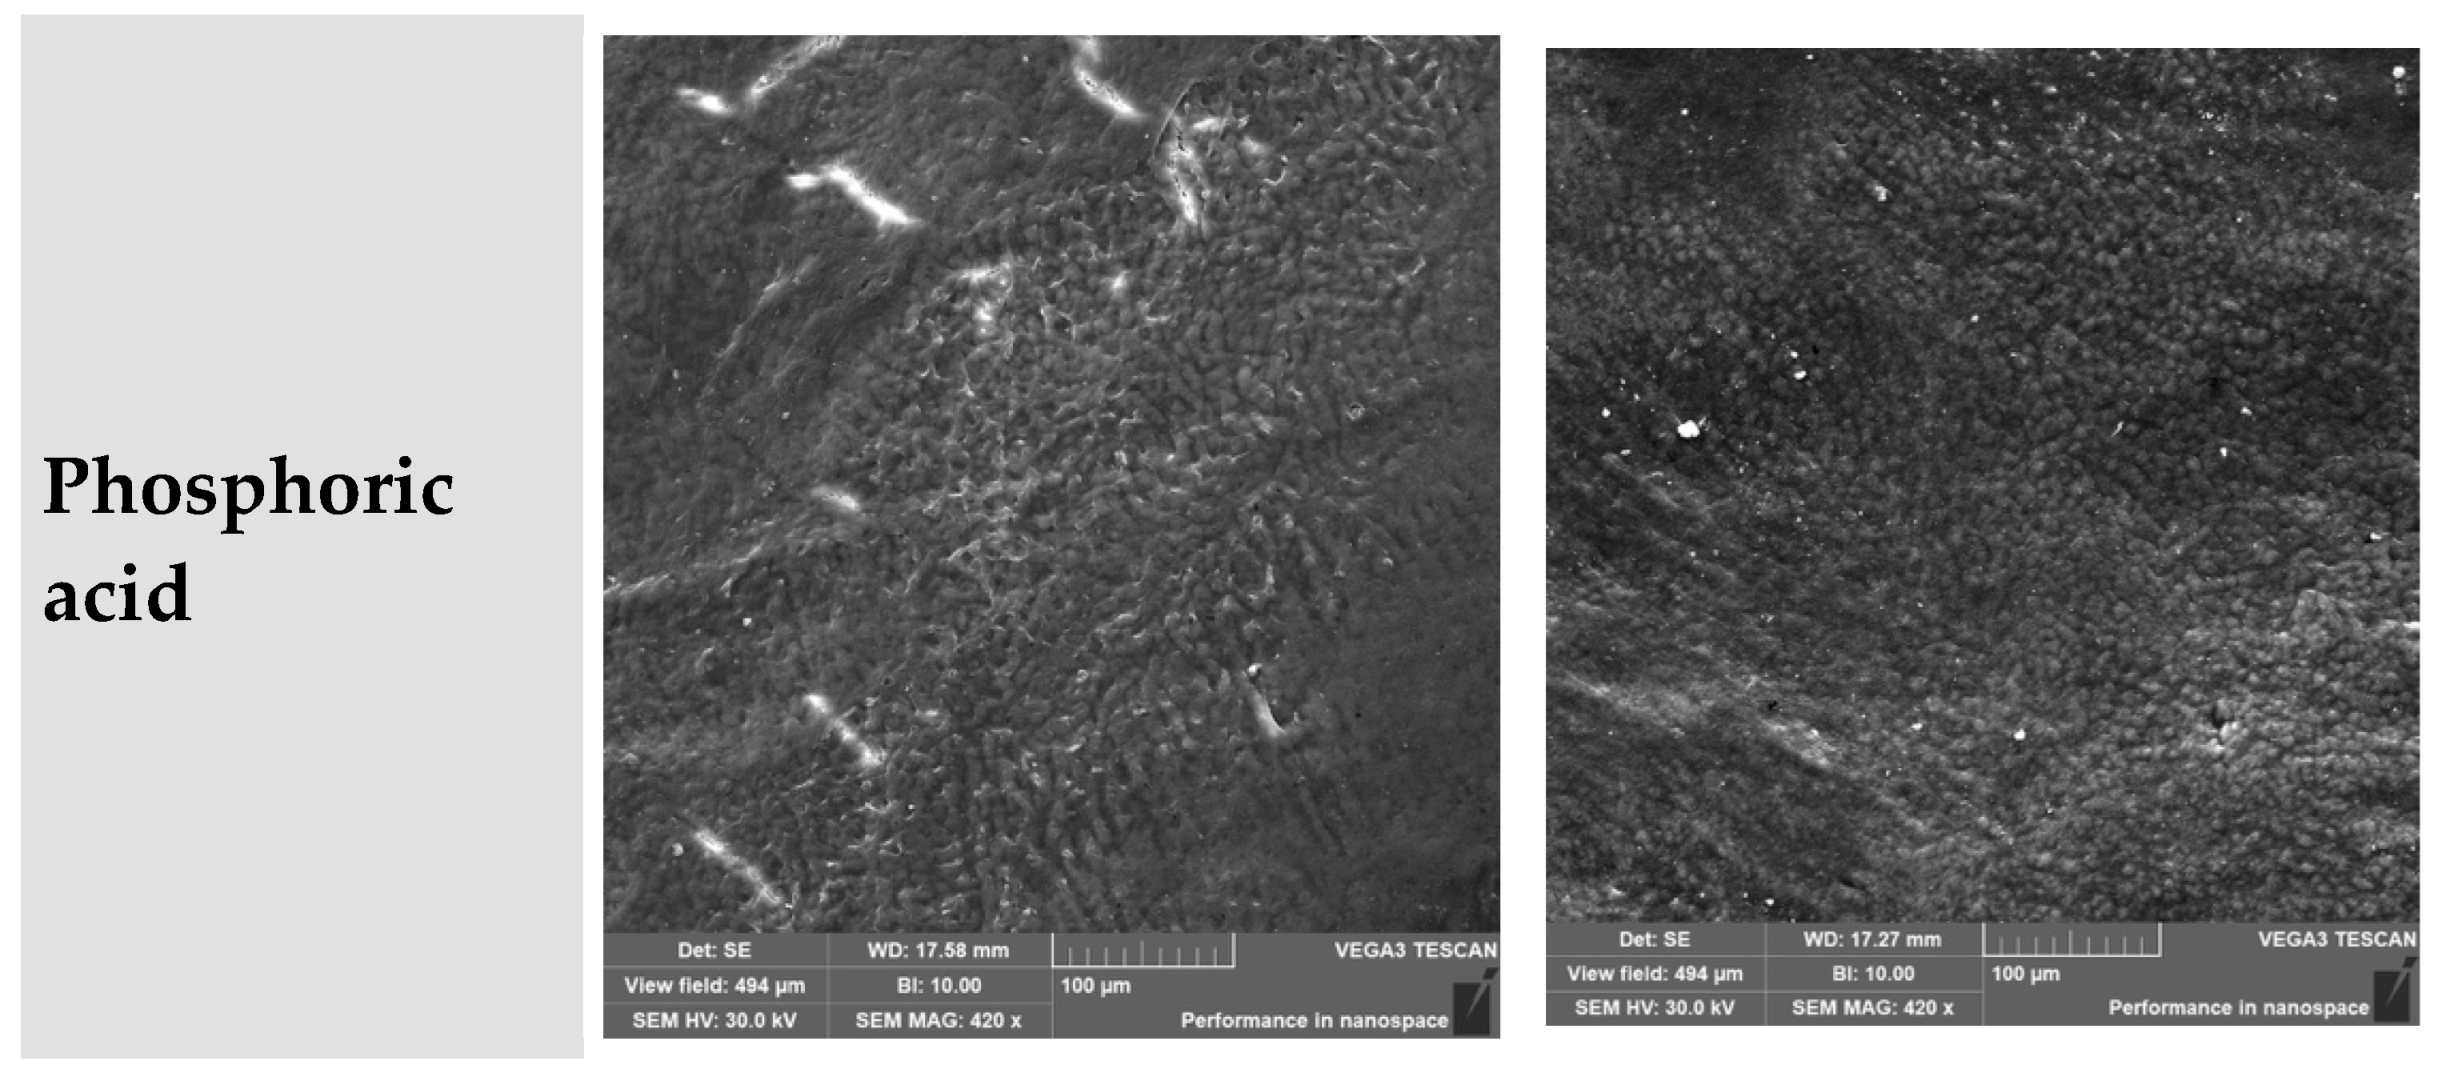

3.9. Phosphoric Acid (H3PO4)

- Coronal third: Ranged from partial to deep etching, depending on the subgroup.

- Middle third: Severely degraded in all specimens.

| Phosphoric acid | Destruction, full tubule exposure, deep erosions | Excessive | Matrix breakdown, fiber separation, loss of continuity | Aggressive agent, high damage risk |

| Phosphoric acid | Ranging from relatively smooth to fully degraded; shallow to deep erosion | Loose, granular, variable depth of cementum destruction | Phosphoric acid induces aggressive demineralization, especially in depth |